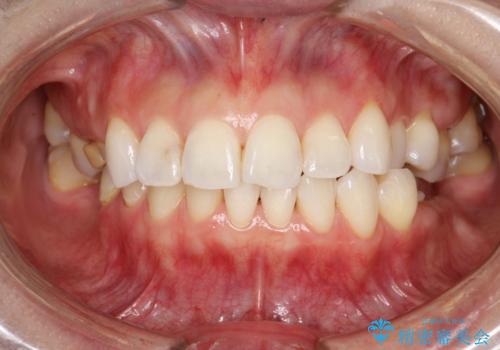

PMTC30分コース(保険外治療)を行いました。かなり久しぶりの歯科医院へ来院とのことで、プラーク(歯垢)・歯石・ステイン(着色)が付着していました。汚れを除去し、本来のご自身の歯質にすることでなにか異常があった際に発見しやすくなります。

PMTCで汚れを除去することは、虫歯や歯周病・口臭予防に効果的です。

また、今回はクリーニング後に、何か所か虫歯や治療途中のままの部分が発見されました。今後は定期的なメンテナンス・クリーニングと併用しながら虫歯の治療を行っていく予定です。